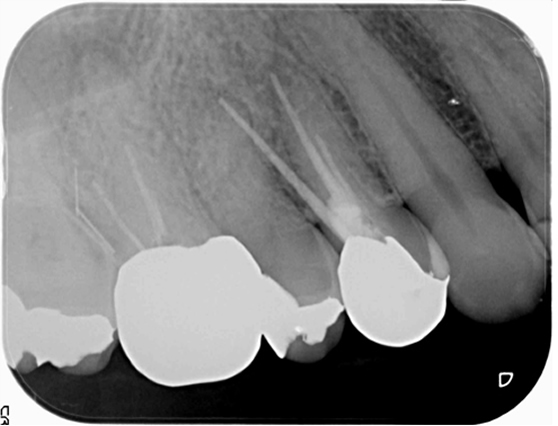

右上4番(右から2番目の歯)を再治療したが治らないとのことで来院。診査したところ、原因は右上5番(右から3番目)の歯の神経が死んでしまっていたためでした。右上5番は通常通り根管治療を行いました。

同時に右上6番に違和感を感じているとのことでしたが、右上6番には歯の横に穴があいており、破折器具が残っている状態でした。破折器具を除去し、根管治療を行いました。(骨内に残った器具は感染源となっておらず、症状が完全に消失したため外科を避けて経過観察としました。その後1年半の経過観察で良好な経過を送っています。